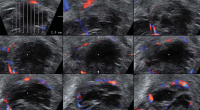

Tipps und Tricks im Gyn-Ultraschall: Sonographische Kennzeichen des Corpus luteum

Journal für Gynäkologische Endokrinologie 2013; 7 (4) (Ausgabe für Österreich): 24-26 Journal für Gynäkologische Endokrinologie 2013; 7 (4) (Ausgabe für Schweiz): 28-30 Volltext (PDF) Abbildungen